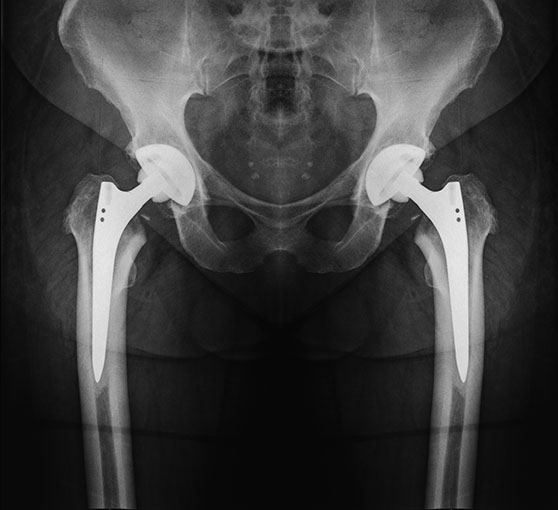

As the disease progresses you may consider some of the many available injections as a way to eliminate pain. This is only a temporary fix however. In the later stages of the disease, total hip replacement surgery can help to alleviate severe pain and restore mobility.